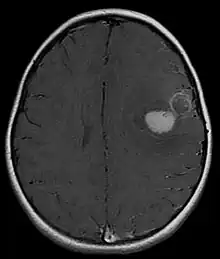

Supratentorial central PNET in a 5-year-old patient

PNET of the CNS generally refer to supratentorial PNETs.

The approach to management of a CNS PNET is first to obtain detailed imaging through MRI, as well as additional scans of the patient's body (X-ray, CT, PET, even bone marrow biopsies) to look for metastasis or other associated malignancies. The tumor will then need to be biopsied to confirm the diagnosis. After the diagnosis of a CNS PNET is confirmed, management includes neoadjuvant chemotherapy and radiation (to reduce tumor size burden), complete surgical resection with confirmed negative margins, and/or additional adjuvant post-surgical chemotherapy. CNS PNET is aggressive and must be managed as so. Palliative care services should also become involved in the patient's care team when the diagnosis is made. [6]